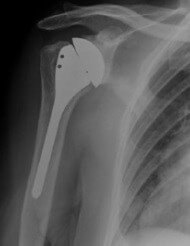

Shoulder Hemiarthroplasty

A shoulder hemiarthroplasty (also means partial shoulder replacement), involves removing the humeral head and replacing it with a metal implant.

Then the stem of the implant is inserted into the medullary canal (the hollow middle of the upper arm bone) and will either be wedged tightly in place or secured with special bone glue cement.

The shoulder head "ball" is then attached to the top of the stem.

Most of the time, a shoulder hemiarthroplasty is done where the fracture is especially complex or if other treatment methods have failed.

Maybe it is an anatomical neck fracture, a four-part fracture, a fracture dislocation, or the rotator cuff may have also been damaged.

Also, if the blood supply to the humeral head has been

compromised plus if there is a high risk of osteonecrosis (where the bone starts to rot and dies), then your shoulder surgeon will likely refer a hemiarthroplasty to be the treatment of choice.